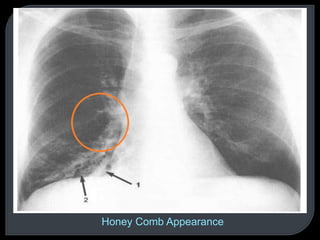

This document discusses x-rays and radiographic views. It begins with the discovery of x-rays by Wilhelm Conrad Roentgen. It then covers basic concepts like radiopacity and radiolucency. Several standard radiographic views are described like AP, PA, lateral, and decubitus. The document outlines how to analyze a chest x-ray using the ABCD method and lists common abnormal radiological signs. Radiographic technique factors like centering and inspiration level are also addressed.